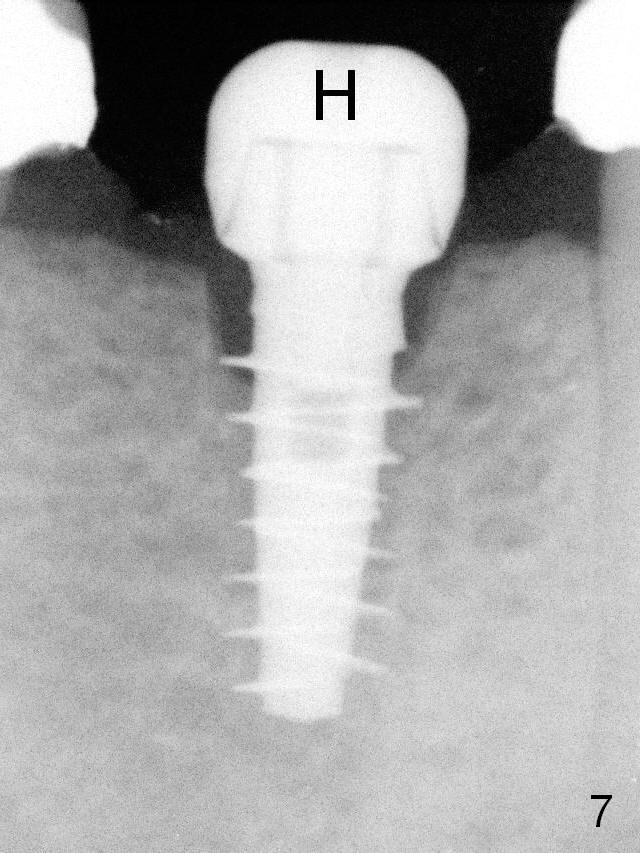

A 4.5x9(1) mm Magicore is placed with 35 Ncm (insertion torque) after 4.3 mm Magic Drill; a 4.5 mm healing abutment is inserted (Fig.7 H).  An error occurs because of using 1 mm cuff of the Magicore.  Ideally 3 or 4 mm cuff should have been used because of reduction in the ridge by ~ 3 mm (Fig.2).  The result of the error is failure of placing the implant at the desirable depth (<9 mm).  The coronal threads are exposed and have to be covered by bone graft (autogenous bone and allograft (.5-1.5 mm) (Fig.8 *), followed by collagen dressing.